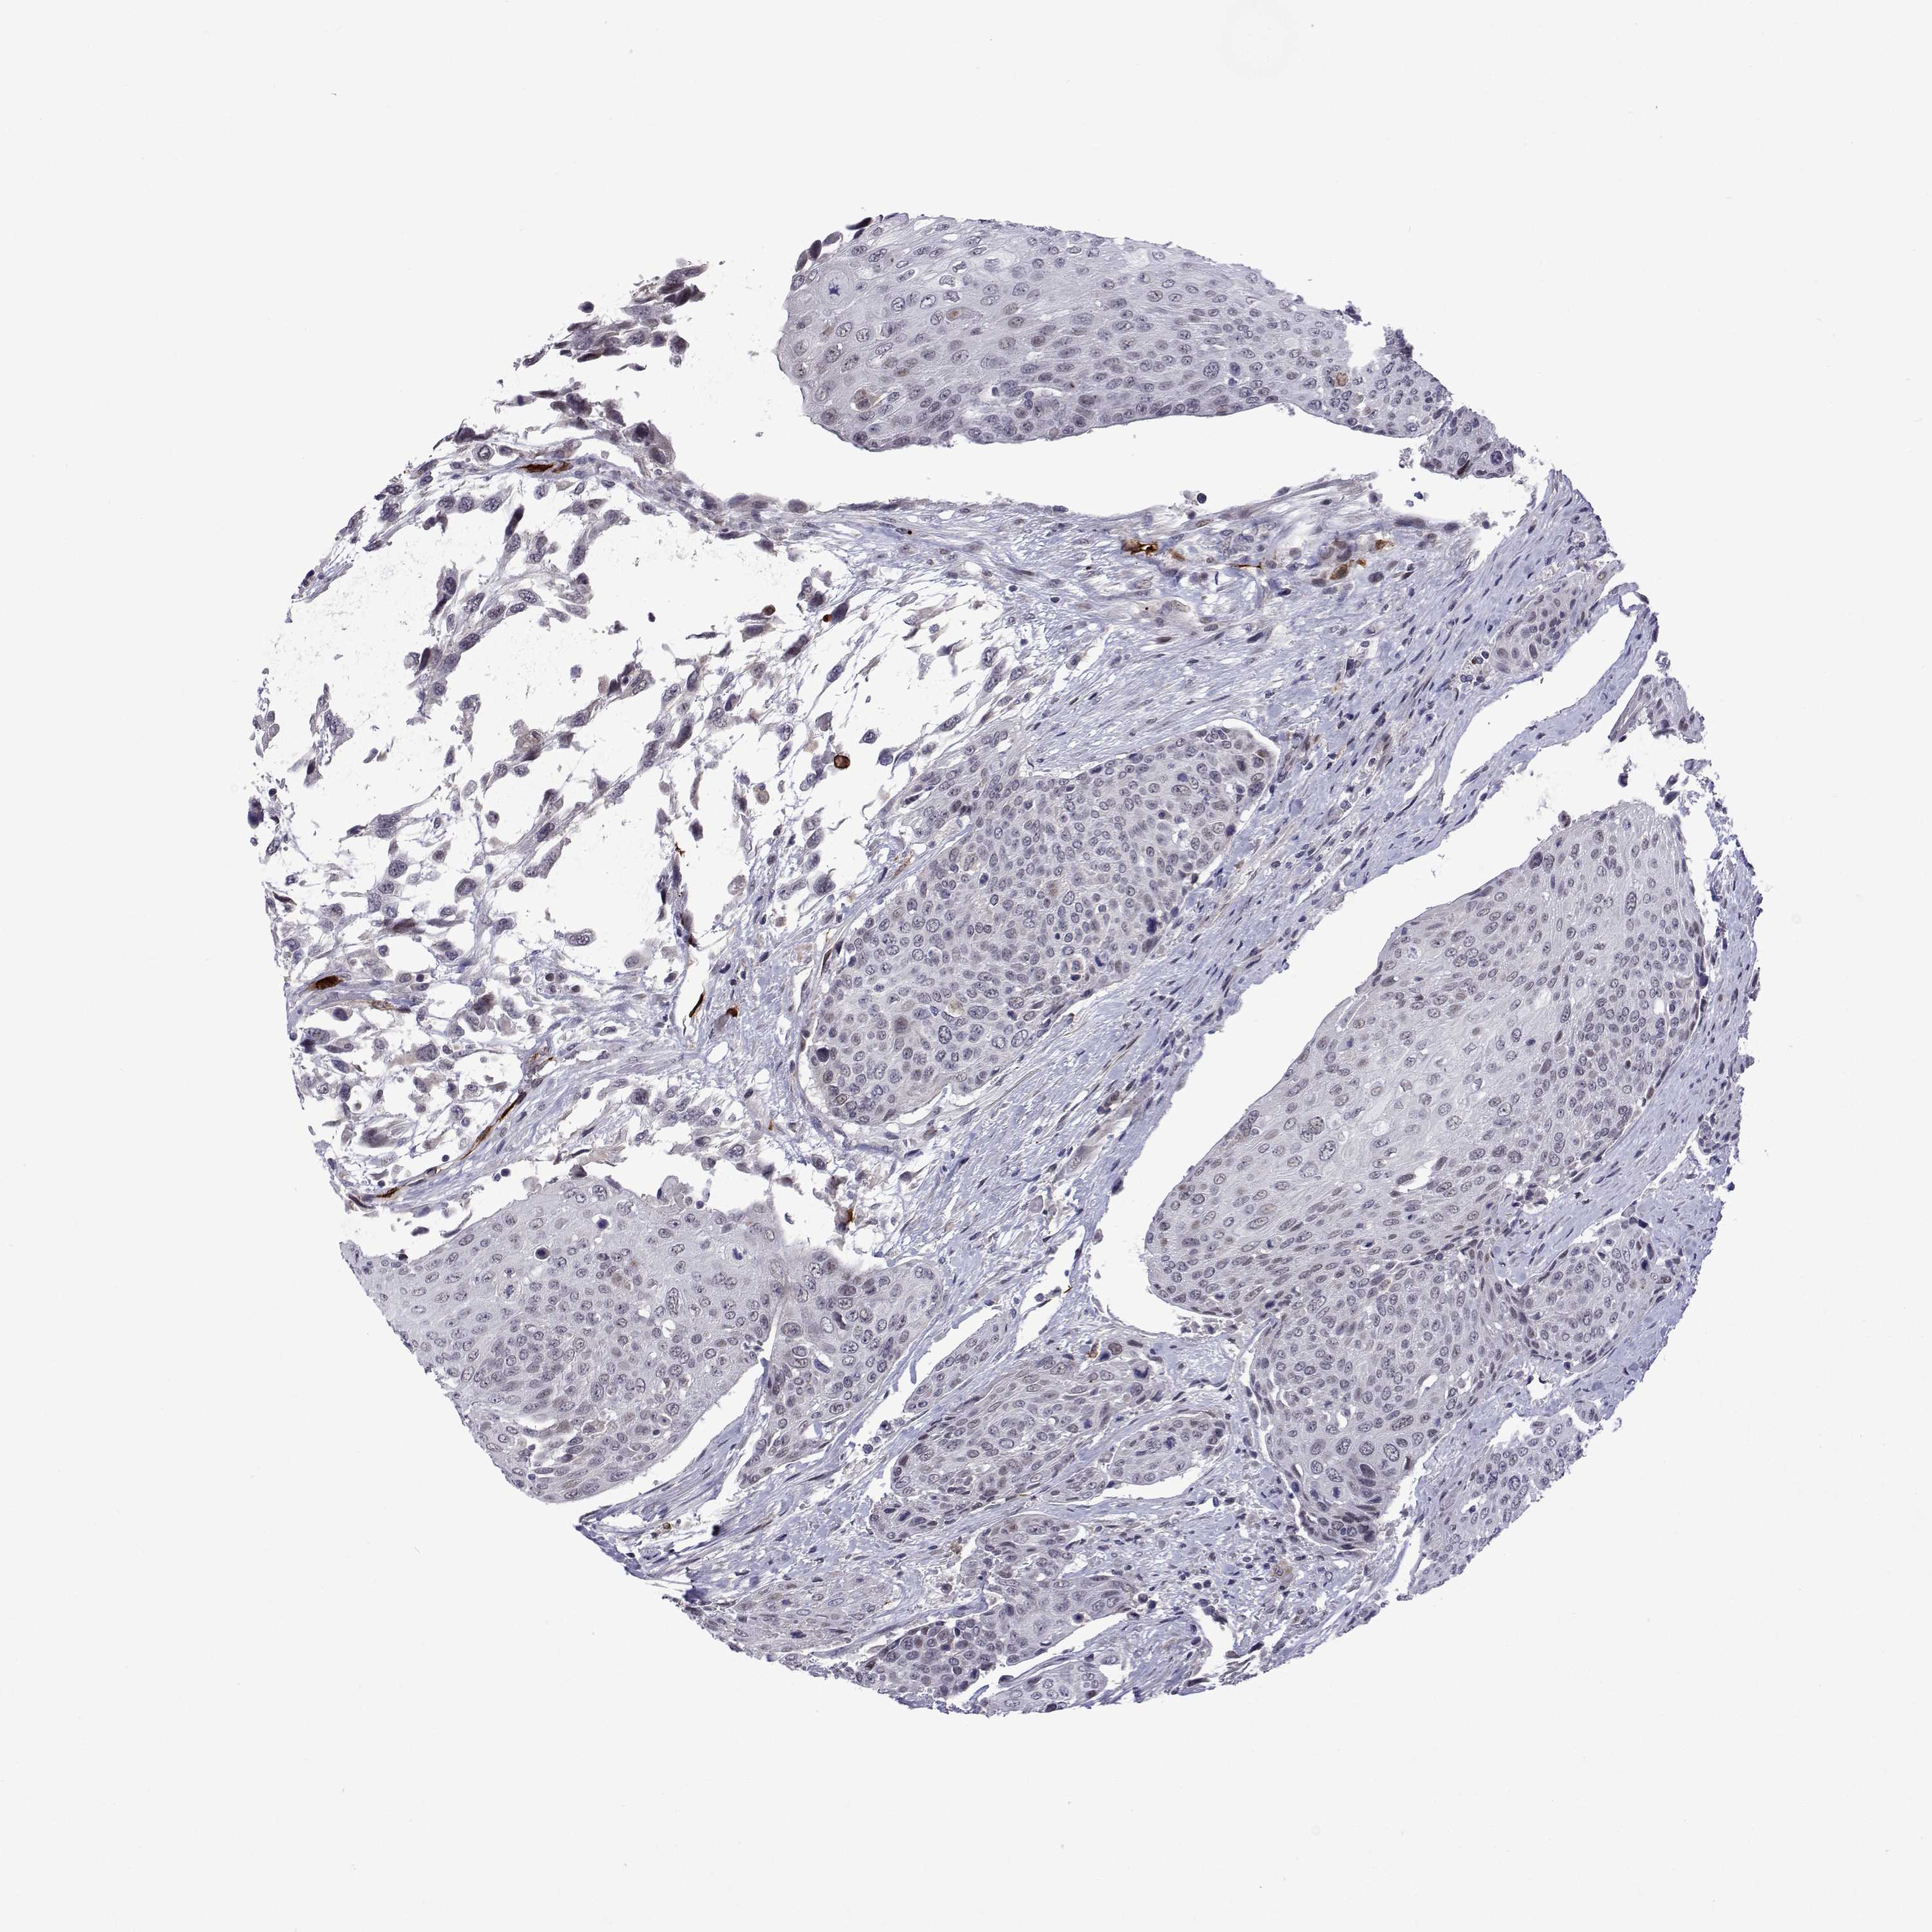

UROTHELIAL CANCER - Protein expressioni

A mouse-over function shows sample information and annotation data. Click on an image to view it in a full screen mode. Samples can be filtered based on level of antibody staining by selecting one or several of the following categories: high, medium, low and not detected. The assay and annotation is described here.

Note that samples used for immunohistochemistry by the Human Protein Atlas do not correspond to samples in the TCGA dataset.

Antibody stainingi

Antibody staining in the annotated cell types in the current human tissue is reported as not detected, low, medium, or high, based on conventional immunohistochemistry profiling in selected tissues. This score is based on the combination of the staining intensity and fraction of stained cells.

Each image is clickable and will lead to virtual microscopy that enables deeper exploration of all samples and also displays staining intensity scores, fraction scores and subcellular localization as well as patient and tissue information for each sample.

Antibody HPA046862

Staining

High

Medium

Low

Not detected

Intensity

Strong

Moderate

Weak

Negative

Quantity

>75%

75%-25%

<25%

None

Location

Nuclear

Cytoplasmic/membranous

Cytoplasmic/membranous,nuclear

Urothelial carcinoma, High grade

Urothelial carcinoma, NOS

Urothelial carcinoma, Low grade